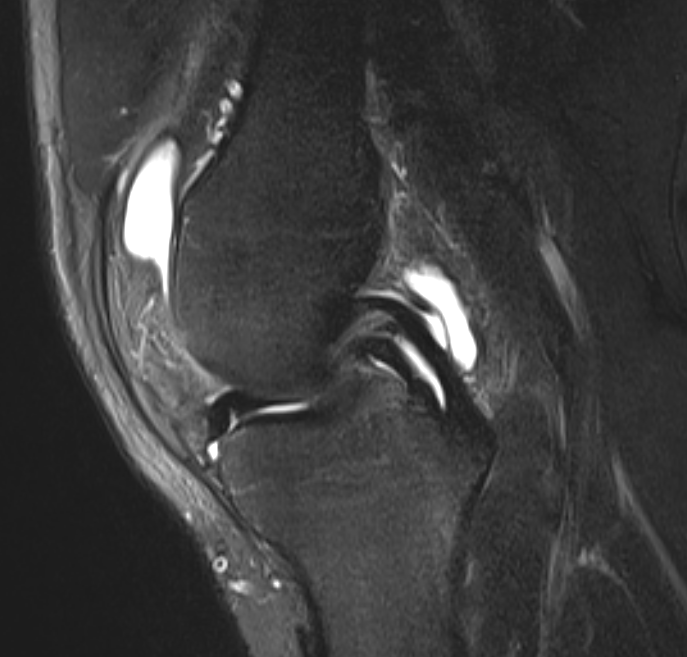

3. Double PCL sign - bucket handle tear of meniscus